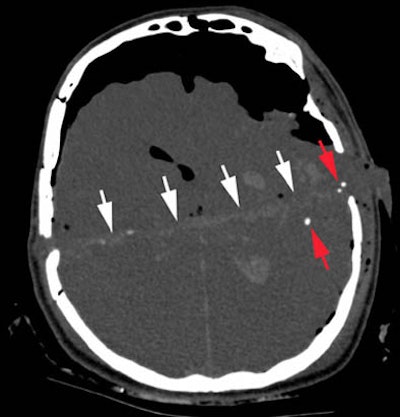

| Axial CT scan displaying intracerebral wound track (white arrows) in a case of suicidal gunshot injury. Note the intracranial air and the bullet fragments (red arrows) along the wound track. Image courtesy of Dr. Michael Thali. |